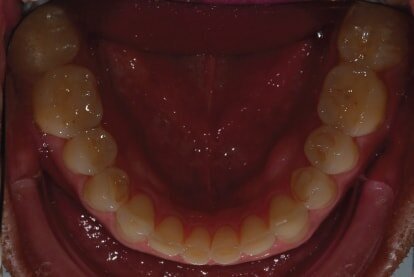

In 2015, a 47-year-old male patient presented complaining of pain in the TMJ. He also had an aesthetic request, since part of the veneer on one of the maxillary central incisors had broken off (Figs. 1–3). The clinical and radiographic analysis (Fig. 4) indicated a loss of bite height and tooth substance due to bruxism.

Fig. 3: Intraoral

photograph prior to treatment, occlusal view of mandible.